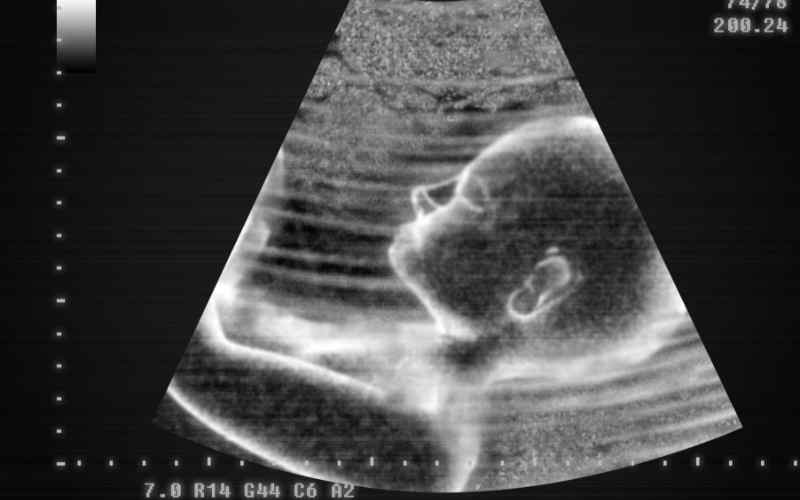

Theo lời khuyên của các chuyên gia, từ tháng 7 của thai kỳ trở đi, bà bầu nên đi siêu âm 2 lần/tháng để theo dõi sát sao quá trình phát triển của bé. Thời gian tốt nhất để đi siêu âm thai là tuần 24-26 của thai kỳ.

Lúc này, các bộ phận trên cơ thể bé đã hình thành đầy đủ và thể hiện rõ nét hơn. Trong quá trình siêu âm, bác sĩ sẽ kiểm tra lượng nước ối, xác định vị trí của thai nhi và tình trạng nhau thai.